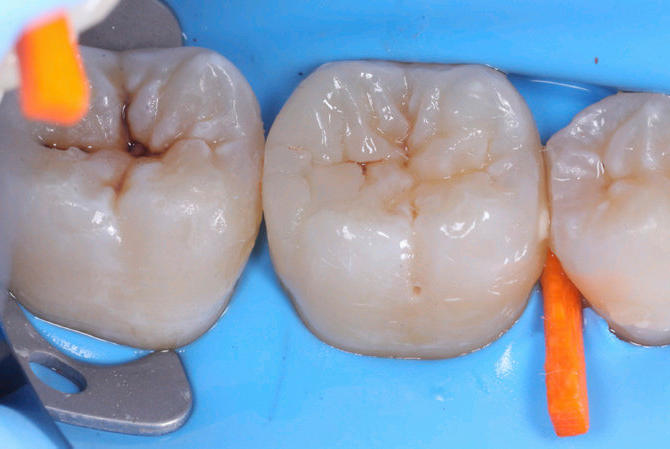

A questo punto si trasforma la seconda classe in prima attraverso la stratificazione della parete inter-prossimale e si prosegue con la modellazione occlusale eseguita cuspide per cuspide

| Fig.5 Aspetto vestibolare del restauro ultimato | Fig.6 Controllo occlusale |